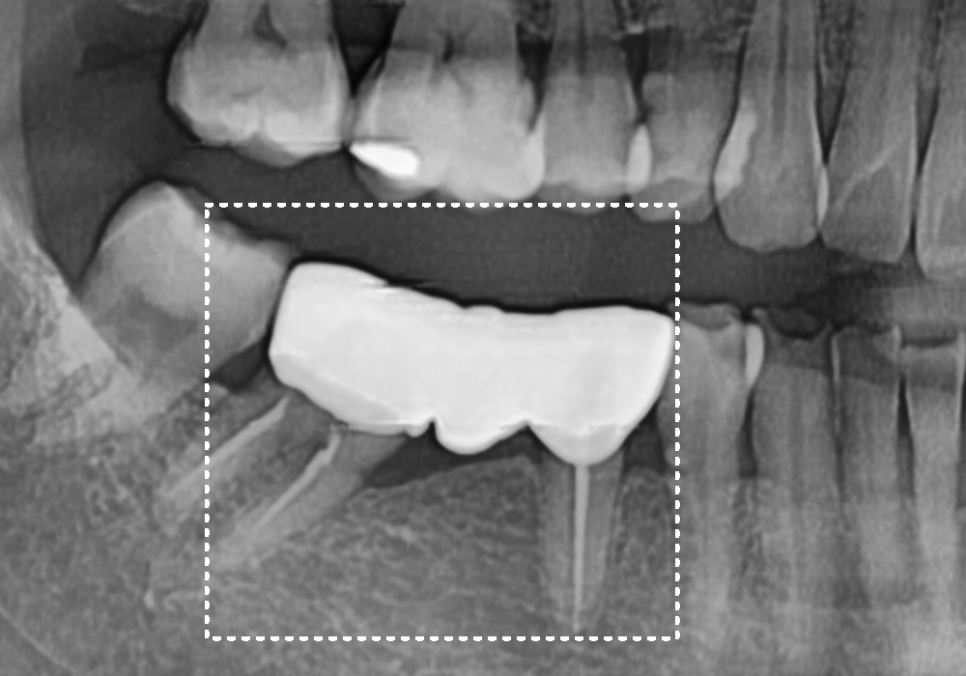

결국, 고민 끝에 교합을 크게 바꾸지 않으면서

빈 곳을 채우는 브릿지로 치료를 결정했습니다.

현재 치아가 많이 기울어져 있기 때문에

치아를 깎는 양이 많을 것으로 예상되었는데요~

시린 증상을 방지하기 위해

꼼꼼하게 신경치료를 선행한 뒤

브릿지로 마무리해드렸습니다~

230704